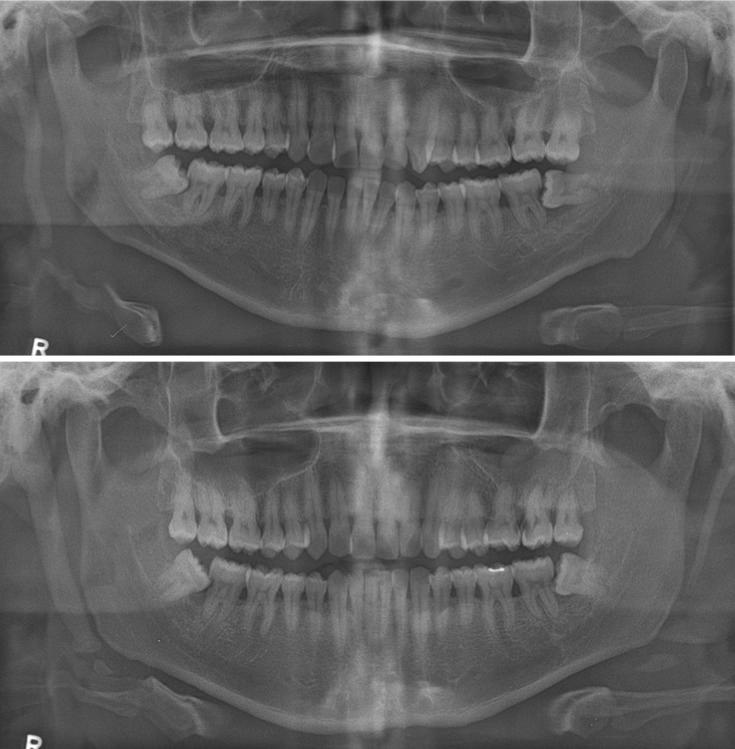

The styloid process is a cylindrical, long cartilaginous bone located on the temporal bone. The calcified stylohyoid ligament and elongated styloid process can be identified radiographically, and they are associated with a number of syndromes and symptoms. The exact cause of the styloid process elongation due to calcification and subsequent ossification of ligament is unclear. This report presents a case of severely calcified stylohyoid ligament complex occurred in twins who have the same pattern of calcification.

茎突是位于颞骨上的圆柱形长软骨性骨。钙化的茎突舌骨韧带和伸长的茎突可通过影像学检查识别,它们与多种综合征和症状相关。韧带钙化及随后骨化导致茎突伸长的确切原因尚不清楚。本报告介绍了一对双胞胎中发生的严重钙化的茎突舌骨韧带复合体病例,他们具有相同的钙化模式。